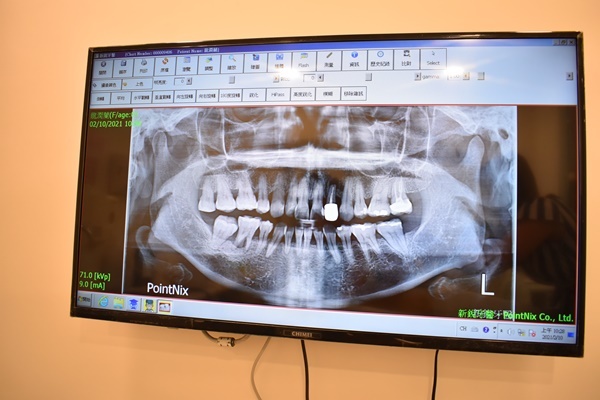

透過諮詢師的介紹還有初步的3d立體X光檢查牙齒後,我才知道我的牙齒

表面看起來風平浪靜,其實在刷不到的死角都有些小蛀牙了,帶上隱形牙套矯正前,

只好請曾仁芬醫師先幫我補我的小蛀牙~